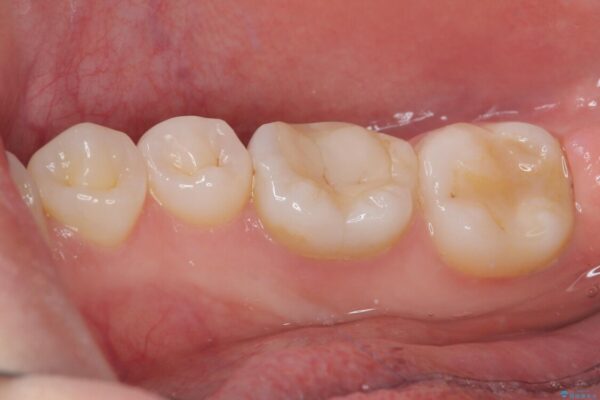

治療後

• ラバーダム使用で再感染リスクを抑えた再根管治療+精密な補綴による長期安定を実現 治療後画像

当院ではラバーダム防湿をし、根管内の感染源をしっかりと除去するために再根管治療を行いました。

その後、ファイバーコア(グラスファイバー製の支台)を築造し、最終的には精密な適合性と審美性に優れたオールセラミッククラウンによる補綴をしました。

このセラミッククラウンは、歯科技工士と連携し、1本1本の形・色・噛み合わせまで細部にこだわって製作しており、見た目の自然さだけでなく、長期的に安心して噛める機能性も重視しています。